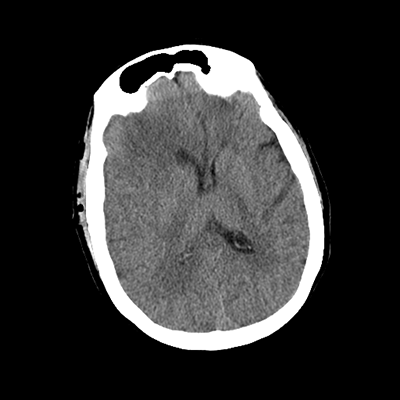

An 76 year-old man with HTN, CAD s/p PCI (two years prior), and PAD initially presented to the ED with subacute left hemiparesis and gait difficulties. He was found to have a large right frontal tumor. He was admitted to the NCCU, and then undergoes a craniotomy for tumor resection later in the week. A post-op head CT is obtained.

There are expected post-operative changes, along with some scant hemorrhaging along the posterior and inferior aspects of the surgical bed. We'll want to ensure that this hemorrhage is stable with a repeat scan, at which point we can start DVT chemoprophylaxis-- will end up being between 24-48 hours post-op.